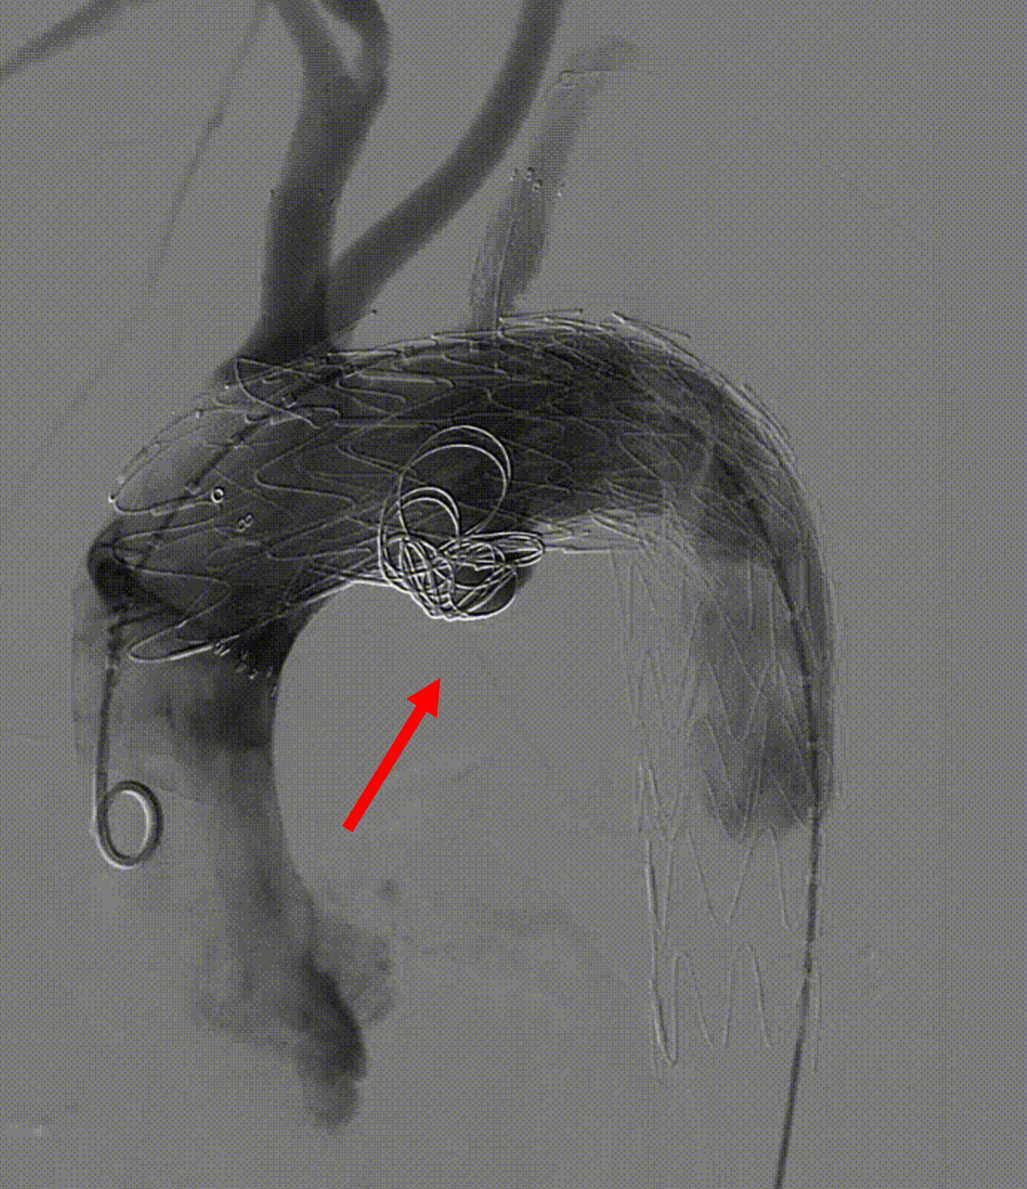

【病例3】B型夹层,TEVAR术后Ⅱ型内漏

复杂病例再干预方案:联合应用栓塞、覆膜支架及封堵器

第二次术前造影,证实为LSA所致Ⅱ型内漏

LSA置入覆膜支架后造影,内漏消失